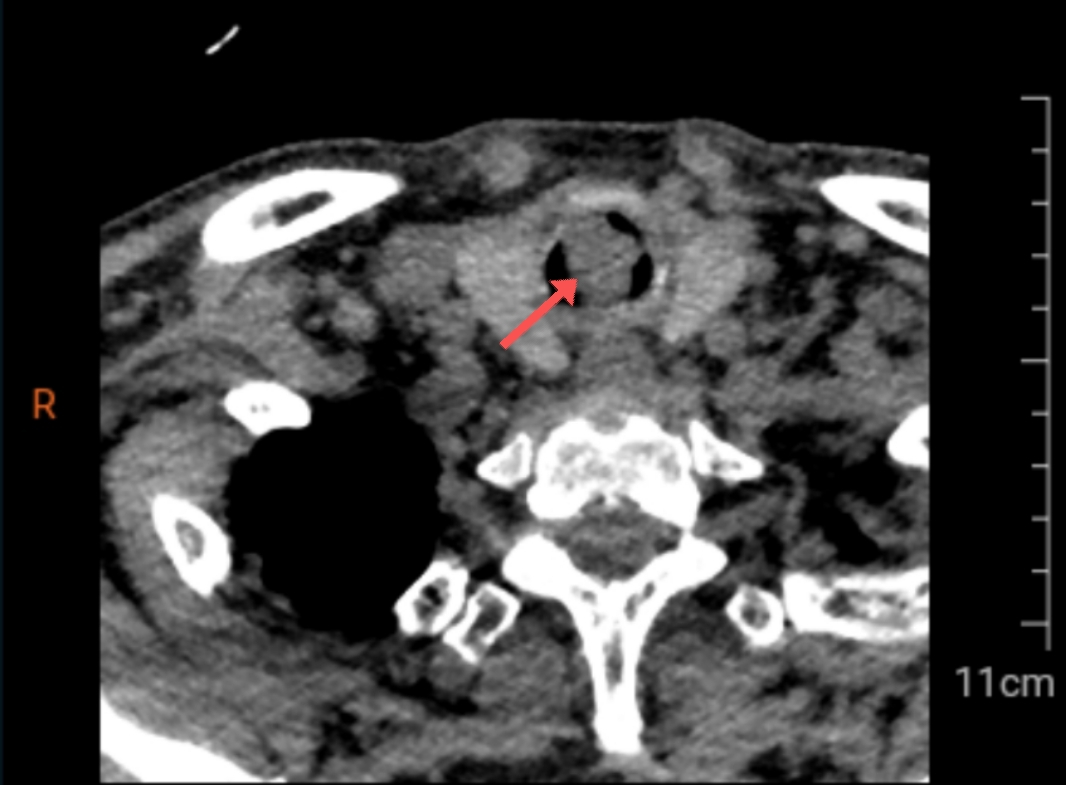

医生通过胸部CT图像发现,在高大爷的气管内距离声门下约1.5公分处有一个肿物,几乎完全堵塞了气道。找到了呼吸困难的原因,医生认为必须进行紧急手术解除梗阻,否则高大爷随时有可能猝死。因此,呼吸与危重症医学科二病区介入团队迅速完成术前准备,在麻醉科的协助下为高大爷完成了全麻下硬质气管镜下肿瘤切除术+APC+冷冻术,一颗大小约1.5*2.0cm的肿物从高大爷的气管内被分离出来。从进镜到铲切肿瘤,仅用时短短20分钟,手术过程非常顺利。